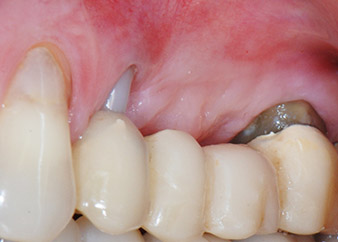

58-годишна пациентка се оплаква от болка и повишена подвижност в нейния мост върху зъб 24 с функция на абатмънт. На лице е периодонтално възпаление с дълбочина на джоба 7 mm мезиобукално и повече от 12 mm дистално, както и включена 3 градусова фуркация. Освен това, рентгенографията показва обширна периодонтална лезия около апикалната зона на (друго място) предварително ендодонтски обработен зъб 24 (Фиг. 1).

След един месец, в деня на операцията, болката и възпалението в зъб 24 е минимално, но подвижността в Miller class 2 е на лице. След отваряне на ламбата и почистването на периапикалната и перирадикуларната тъкани, обхватът на костния дефект стана очевиден (Фиг. 2 и 3).

В букалния корен, цялата вестибуларна и дистална кост липсва. Захващането е значително ограничено до палатиналния корен, подчертавайки предварително лошата прогноза. Зъб 27 също откри намалено хоризонтално захващане и минимално апикално разреждане (Фиг. 1) без клинични симптоми.